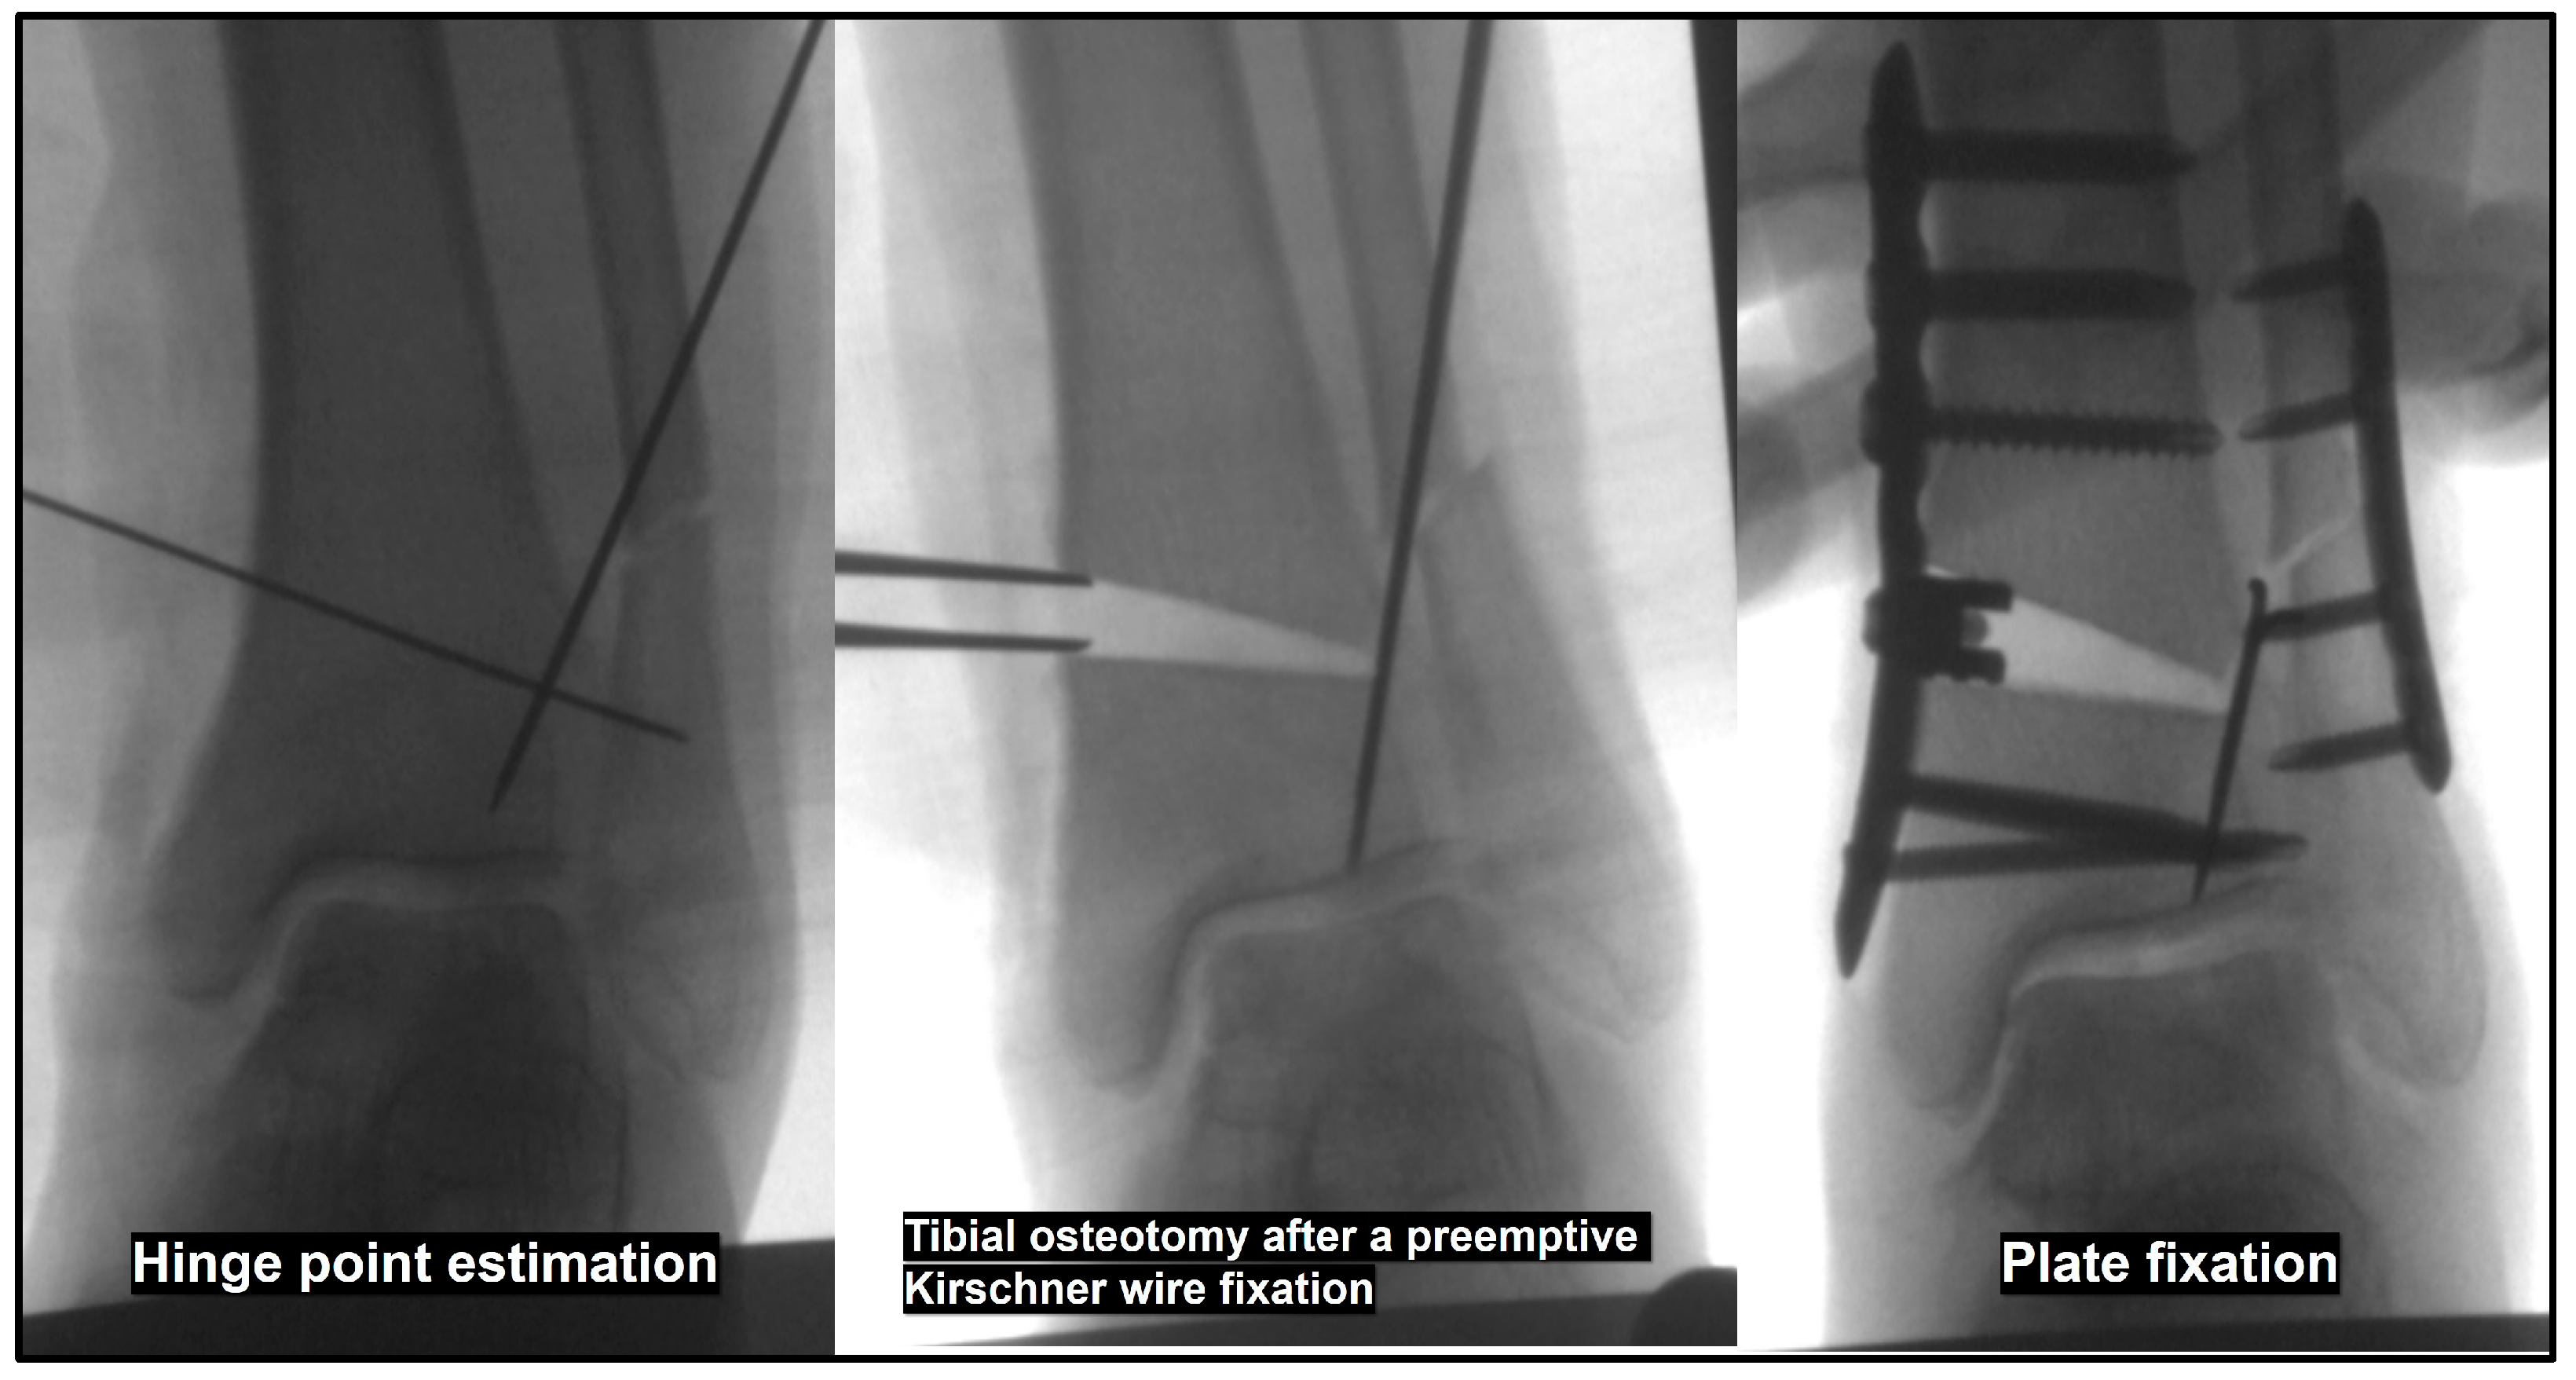

- Preemptive Kirschner wire fixation at the anticipated tibial hinge site

- Opening of the tibial osteotomy site, followed by plate fixation with a metal wedge or tricortical bone graft

- Choi, J.Y.; Suh, J.S.; Song, T.H. Protective Kirschner wire fixation to reduce the effect of lateral hinge fracture during the medial opening wedge low tibial osteotomy: A technical note. Tech. Orthop. 2024, 39, 17–19. [Google Scholar] [CrossRef]